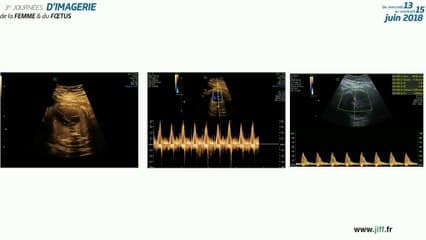

La médiathèque du Collège Français d'Échographie Fœtale (CFEF) constitue l'une des plus importantes collections de ressources vidéo dédiées à l'échographie fœtale en France. Avec plus de 3 261 vidéos, elle couvre l'ensemble des thématiques liées à la pratique échographique prénatale.

Vous y trouverez des conférences présentées lors des congrès nationaux et internationaux, des cours magistraux dispensés par des experts reconnus, des démonstrations pratiques sur des cas cliniques réels, ainsi que des podcasts et tables rondes sur les dernières avancées de la spécialité.